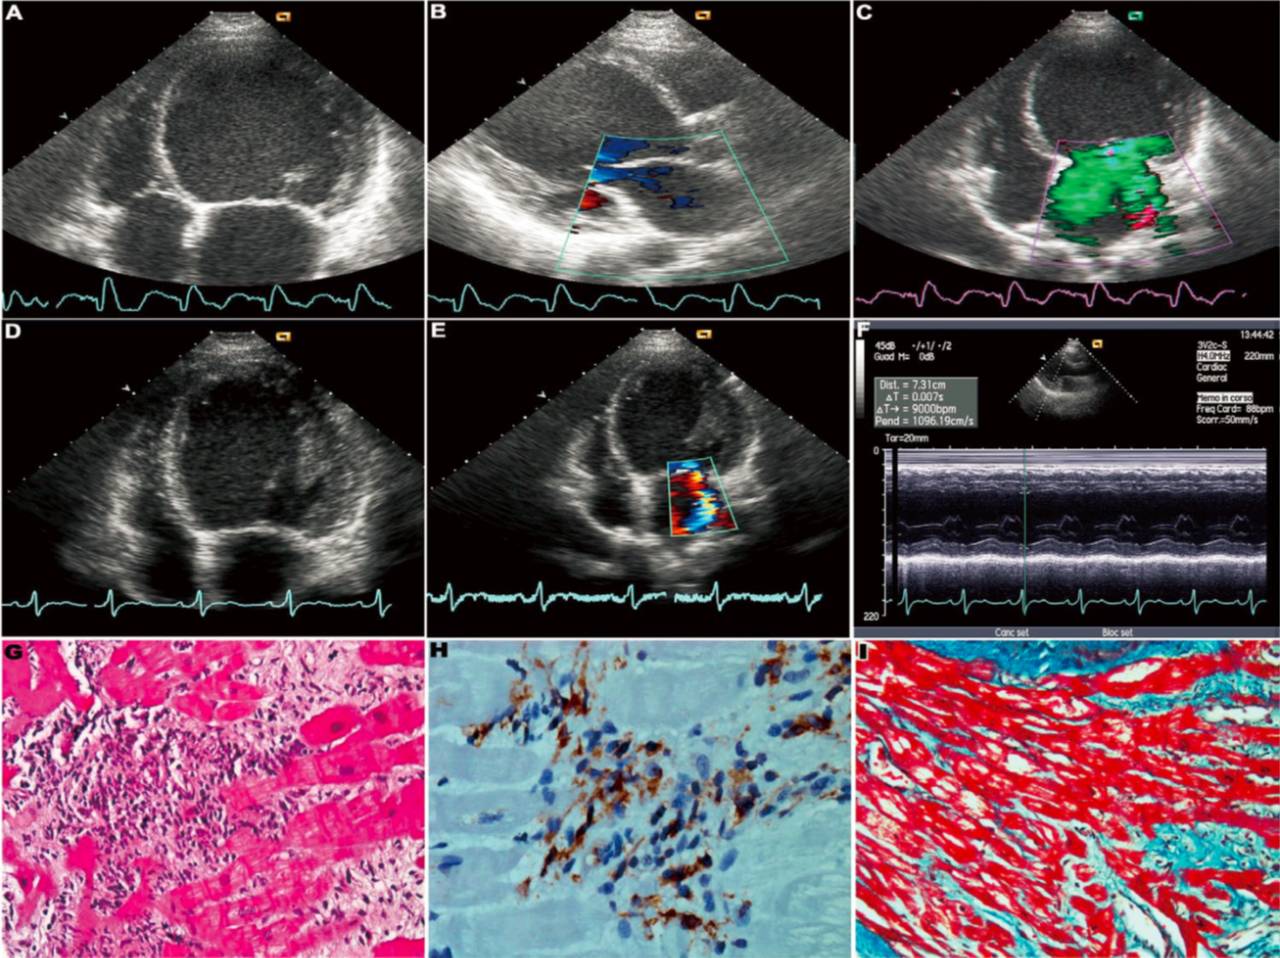

心脏超声心动图(UCG)

②心脏超声心动图(UCG):其评价与以往认识无明显区别,主要用于排除其他心脏疾病如瓣膜病,监测心脏的改变如腔室大小、室壁厚度、心脏功能等,并建议对于所有疑诊心肌炎患者应常规行UCG,当血流动力学发生变化或症状恶化应及时复查UCG。

免疫抑制剂治疗好转1例